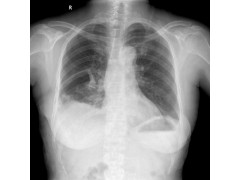

肺大泡(pulmonary bulla)(也作肺大疱)是指由于各种原因导致肺泡腔内压力升高,肺泡壁破裂,互相融合,在肺组织形成的含气囊腔。目前绝大多数的肺大泡手术均可在电视胸腔镜(VATS)下完成,2/3的患者术后症状明显改善。肺大泡一般继发于小支气管的炎性病变,如肺炎、肺结核或肺气肿,也有一些病因不清的特发性肺大泡。小支气管发生炎性病变后出现水肿、狭窄,管腔部分阻塞,产生活瓣作用,使空气能进入肺泡而不易排出,致肺泡腔内压力升高;同时炎症使肺组织损坏,肺泡壁及间隔逐渐因泡内压力升高而破裂,肺泡互相融合形成大的含气囊腔。让我们一起看看,口碑好的肺大泡,全套肺大泡,咸阳肺大泡的信息吧